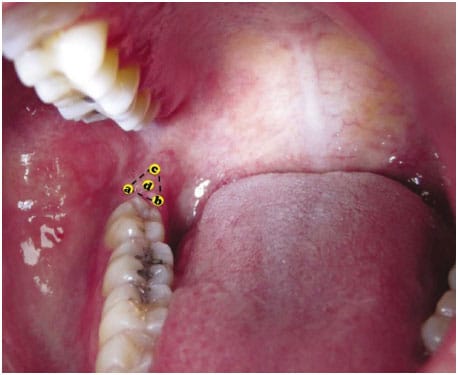

Aquí un experto trata una alteración similar en la zona,

Afta en el trígono retromolar

Presentamos el caso clínico de un paciente de 25 años de edad con un leiomioma en trígono retromolar derecho. Dada la escasa incidencia de este tipo de patología, la edad del paciente y su inusual ubicación, se justifica la presentación de este caso.**